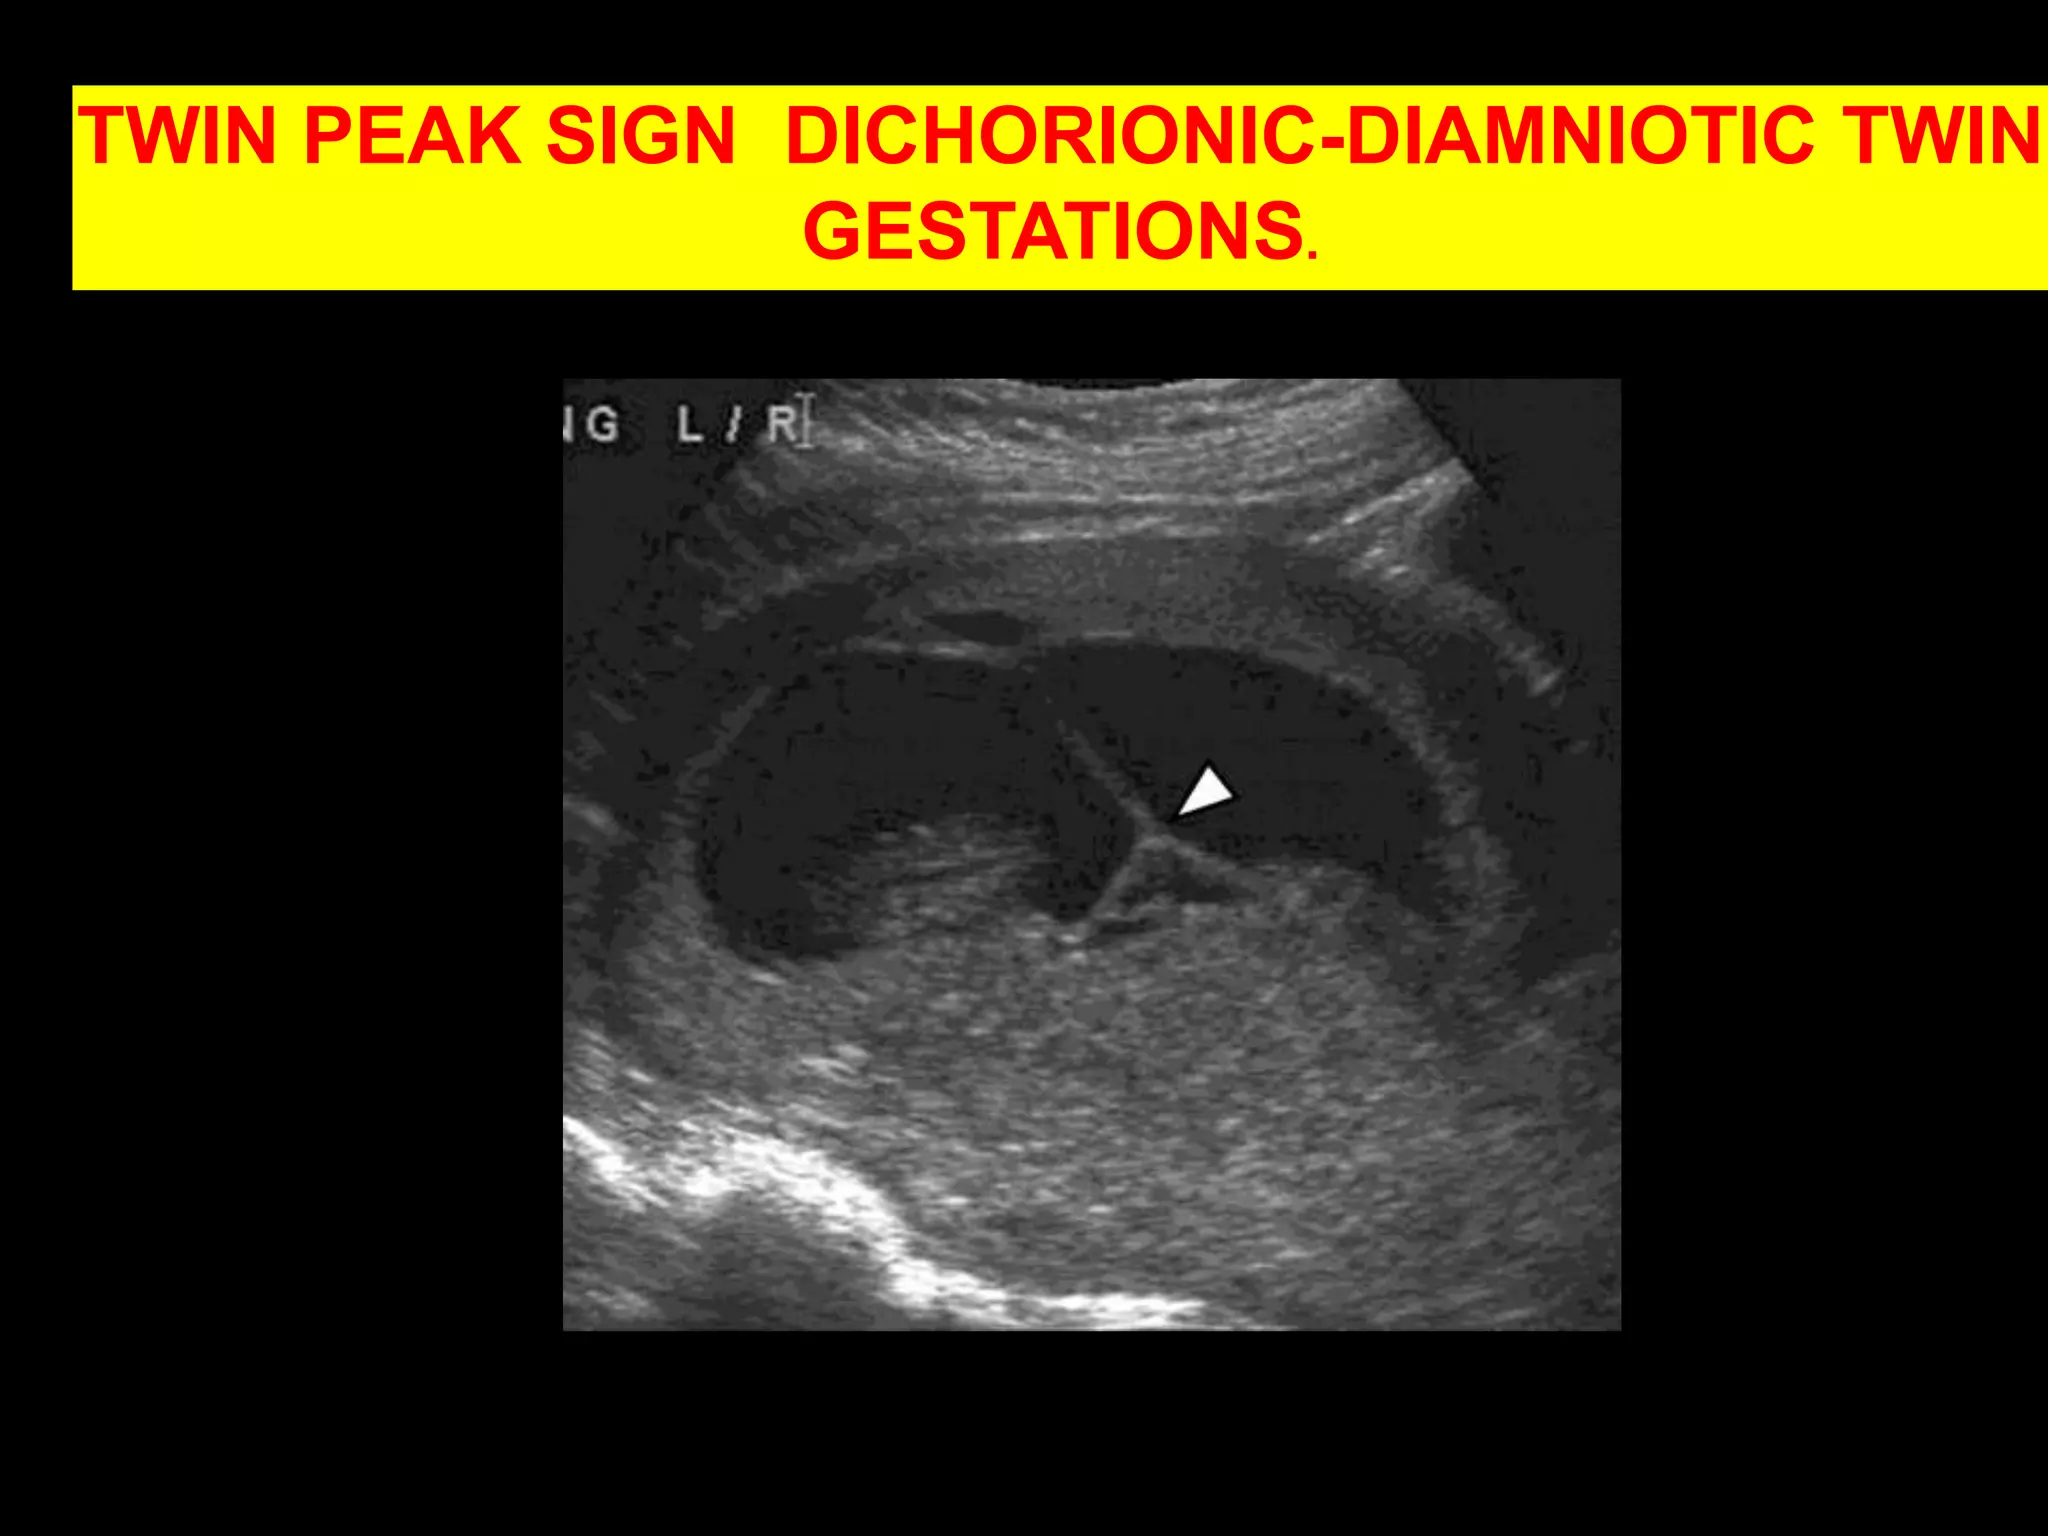

TWIN PEAK SIGN  DICHORIONIC-DIAMNIOTIC TWIN GESTATIONS.©2009 by Radiological Society of North America